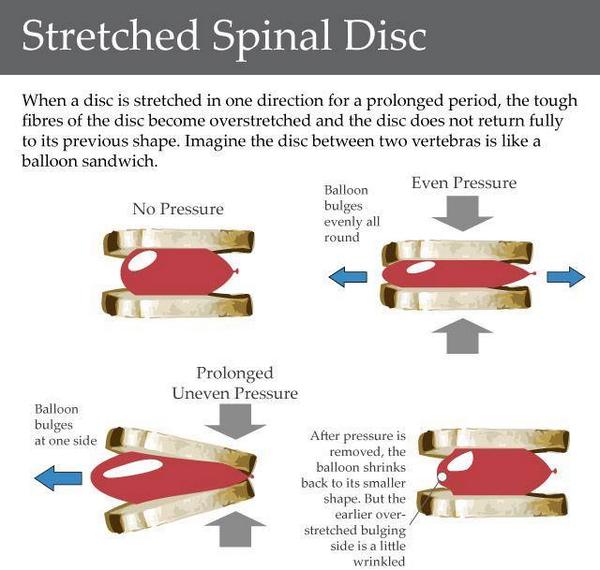

Do you know what a stretched spinal disc is? #wellness #spine #spinaldisc #chiro #chiropractor #backpain

Spinal Disc: The Water Balloon & Jelly Donut Explained! #SpinalDisc #Anatomy #BackPain #HealthEducation #DrGarofalo #MedicalKnowledge #BodyFunction #Wellness #Healthcare #HumanBody

A #spinaldisc is a jelly donut-type structure with the tougher fibrous outer layer and soft gel-like center. mehtaspine.co.uk/blog/what-is-a… #mehtaspineuk

Do you know what a stretched spinal disc is? #wellness #spine #spinaldisc #chiro #chiropractor #backpain